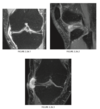

A 16-year-old basketball player with pain in his left knee

A

Sagittal, axial and coronal gradient-recalled echo MR images of the left knee

show a focal area of high signal intensity within the

patellar tendon just below its origin from the infe-

rior aspect of the patella (arrows)

Patellar tendionosis

Overuse syndrome. Chronic repetitive stress without rest may

result in necrosis, fibrosis, and degeneration within

the tendon and may over time lead to tendon rup-

ture.

Sindig-Larsen-Johansson disease = Bony fragmentation of the lower pole of the patella in a young patient. (Osteochondroses)

Figure 2.12.4 is a coned-down,

lateral knee radiograph of a 13-year-old athlete

with anterior knee pain and shows fragmentation

of the inferior pole of the patella (arrow). The sagit-

tal T2-weighted MR image (Fig. 2.12.5) confirms the fragmentation of the patella and shows prepatel-

lar edema and edema within the proximal patellar

tendon (arrow). The sagittal T1-weighted MR image

(Fig. 2.12.6) shows the fragmentation of the patella

that is characteristic of this disorder (arrow).

MRI is the diagnostic investigation of choice to

confirm the clinical suspicion of patellar tendinosis.